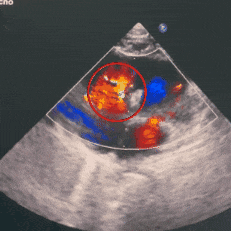

右盘展开后,超声下可见双盘骑跨于室间隔两侧,封堵器呈现“长哑铃”型

锁定后超声下可见封堵器呈“工”字型,盘面平整,贴合良好

释放后超声评估

超声四腔心及主动脉短轴切面观察封堵器形态良好,无残余分流,盘面平整,无周围瓣膜影响